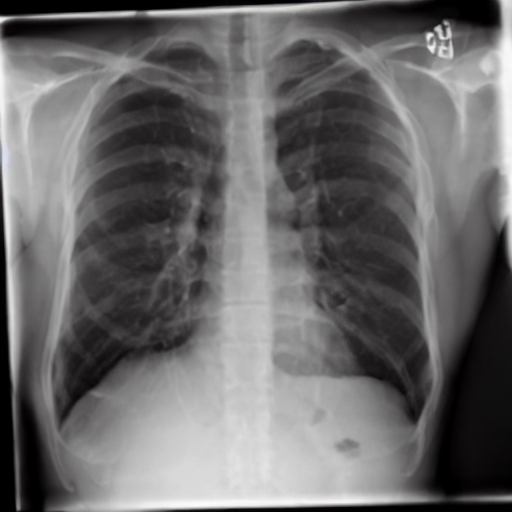

4.1 Qualitative Evaluation of Healthy Counterpart Generation

Example images from the disease COVID-19 Radiography Database and their generative healthy counterparts are given in figure 2. The images on the far left are instances of the lung opacity class from the real images in the dataset. The images in the middle column are examples of the generated healthy counterfactuals obtained via latent space diffusion, with RadBERT-guided textual-conditioning via a conditional prompt “normal chest x-ray”. A total of 75 diffusion inference steps are used with image conditioning strength=0.85 and guidance scale=7.5. (The former indicates the level of constraint on changes to the original input image and the latter is the weight given to the textual encoder conditioning in the generation of the image, ranging over [0,1] and [0,9], respectively).

Side-by-side inspection of the generated healthy counterfactuals (as per fig. 2) suggests that, as required, only minimal perturbation is made to the original image with respect to healthy pixels -i.e. localized image sites without structural medical defects. (In the top row, the medical structural defect in the original image is due to a lung opacity, and characterized via a relatively complex interaction between the imaging modality and subject manifesting as ‘gaps’ in the corresponding portions of the lung scan). The healthy/non-healthy discrepancy maps in all of these cases are obtained via masked subtraction of the original image from the generated image (the ground truth segmentation masks correspond to the broad area of interest –i.e. the complete lung). The generated healthy tissue is thus a subset of the mask and is shown in the final column of fig. 2 for the respective cases.

In the context of a VANT-GAN[20]-based approach, this highlighted material constitutes the diagnostic counterfactual visual attribution, i.e. the selection of material relevant to the diagnosis of the unhealthy condition. Healthy counterfactual generation was performed for the complete datasets in the three unhealthy classes, i.e Lung opacity, Viral Pneumonia and COVID, examples of which are given in fig. 3 for the three classes (all of the generated healthy counterfactuals from this experiment can be found on https://huggingface.co/ammaradeel/diffusionVA). Visual inspection indicates that the generated counterfactuals are, in general, visually plausible with minimal perturbation made to the unhealthy image overall. Moreover, the healthy counterpart generation does not appear to unnecessarily affect aspects of the images unrelated to the medical condition, the model selectively making changes to the unhealthy regions in a structurally plausible manner, e.g. generating missing portions of the lung without generating extraneous lung material where it would be expected to normally exist (e.g. in the abdominal cavity).